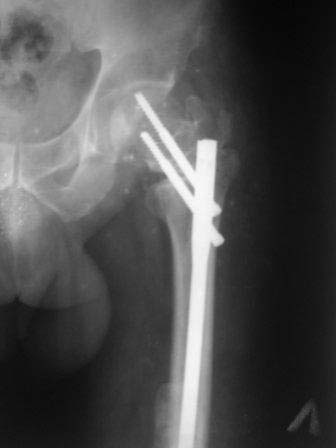

ЭОП унас нет, больной оперирован тогда, 35 дней назад, во время наркоза определена патологическая подвижность в вертельной обл, поэтому произведена остеотомия с исправлением угла, антеградный БИОС ,универсальный стержень ChM. Рентген снимки свежие фас и аксиальная. Пациент ходит с двумя костылями, ногу частично нагружает, лежа выпрямленную ногу поднимает.

... произведена остеотомия с исправлением угла, антеградный БИОС, универсальный стержень ChM...

На мой взгляд угол абсолютно не исправлен, а даже где-то уменьшился (106 гр. против 114), есть все условия для прорезывания шеечных винтов при нагрузке. Если открывали зону перелома, почему не выбрали в качестве импланта клинковую пластину?